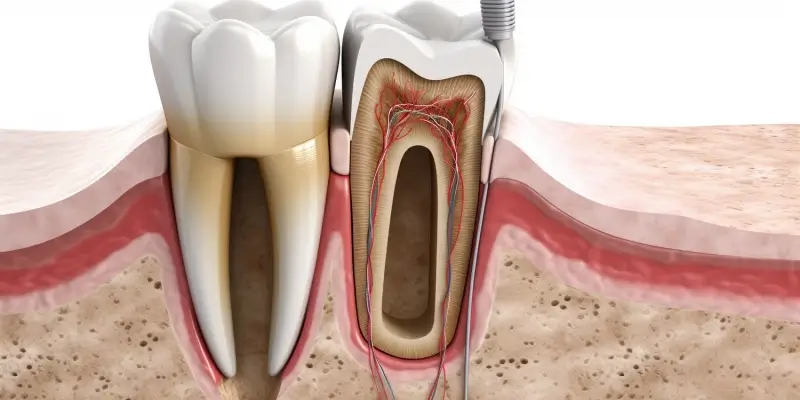

Leczenie kanałowe, znane również jako endodoncja, budzi wiele obaw wśród pacjentów, głównie ze względu na powszechne przekonanie o jego bolesności. Jednak nowoczesna stomatologia dysponuje skutecznymi metodami łagodzenia bólu, a zastosowanie odpowiedniego znieczulenia odgrywa kluczową rolę w komforcie pacjenta podczas tego zabiegu. Pytanie „Czy leczenie kanałowe boli z znieczuleniem?” pojawia się niezwykle często i jest całkowicie uzasadnione, biorąc pod uwagę wrażliwość tej procedury. Celem tego artykułu jest rozwianie wszelkich wątpliwości, wyjaśnienie mechanizmów działania znieczulenia w kontekście leczenia kanałowego oraz przedstawienie, czego pacjent może się spodziewać podczas wizyty u endodonty.

Współczesne techniki anestezjologiczne stosowane w stomatologii są niezwykle zaawansowane. Znieczulenie miejscowe, które jest standardem w leczeniu kanałowym, ma na celu całkowite zablokowanie przewodzenia impulsów bólowych w obszarze zabiegu. Dentysta, dobierając odpowiedni preparat i technikę aplikacji, dąży do tego, aby pacjent nie odczuwał żadnego dyskomfortu ani bólu. Pomimo tego, sporadycznie mogą pojawiać się sytuacje, w których pacjent odczuwa pewien dyskomfort. Zrozumienie przyczyn takiego stanu rzeczy oraz możliwości radzenia sobie z nim jest kluczowe dla pozytywnego doświadczenia pacjenta.

Warto podkreślić, że strach przed bólem często jest większy niż rzeczywiste doznania podczas zabiegu. Dobrze wykonane znieczulenie miejscowe powinno zapewnić pełne odrętwienie obszaru, w którym przeprowadzane jest leczenie kanałowe. Oznacza to, że pacjent nie powinien czuć bólu podczas manipulacji narzędziami endodontycznymi, wiercenia czy płukania kanałów korzeniowych. Wszelkie odczucia, jeśli się pojawią, powinny być łagodne i łatwe do opanowania.

Mimo stosowania skutecznych środków znieczulających, czasami pacjenci zgłaszają odczuwanie bólu lub dyskomfortu podczas leczenia kanałowego. Przyczyn tego stanu rzeczy może być kilka. Jedną z nich jest stan zapalny toczący się w tkankach okołowierzchołkowych zęba. Zaawansowane zapalenie może sprawić, że tkanki będą bardziej wrażliwe, a znieczulenie może zadziałać z opóźnieniem lub nie w pełni zablokować przewodzenie impulsów bólowych. W takich sytuacjach dentysta może podjąć decyzję o zastosowaniu dodatkowej dawki znieczulenia lub o przełożeniu części zabiegu na inną wizytę, aby zapewnić pacjentowi maksymalny komfort.

Kolejnym aspektem jest indywidualna reakcja organizmu na środki znieczulające. U niektórych osób metabolizm leków jest szybszy, co może prowadzić do skrócenia czasu działania znieczulenia. Ponadto, anatomia zęba i jego unerwienie mogą być nietypowe, co czasem utrudnia osiągnięcie pełnego znieczulenia. W takich rzadkich przypadkach dentysta musi wykazać się szczególną ostrożnością i cierpliwością, stosując różne techniki aplikacji znieczulenia, aby zapewnić jak najlepszy efekt.

Nowoczesne metody znieczulenia stosowane w leczeniu kanałowym oferują pacjentom znaczące korzyści, głównie w postaci minimalizacji odczuwanego bólu i dyskomfortu. Preparaty anestetyczne dostępne obecnie są znacznie skuteczniejsze i bezpieczniejsze niż te stosowane przed laty. Wiele z nich zawiera dodatki, które przedłużają czas działania znieczulenia i przyspieszają jego onset (moment rozpoczęcia działania), co jest szczególnie ważne w przypadku długotrwałych procedur, takich jak leczenie kanałowe. Stosowanie odpowiednio dobranego środka znieczulającego pozwala na pełne odrętwienie obszaru zabiegowego, dzięki czemu pacjent nie odczuwa bólu podczas pracy narzędzi endodontycznych, wiercenia czy płukania kanałów.

Kolejną istotną zaletą jest możliwość zastosowania różnych technik podania znieczulenia. Oprócz tradycyjnych metod iniekcyjnych, popularność zdobywa znieczulenie komputerowe. Systemy te pozwalają na bardzo precyzyjne i stopniowe podawanie środka znieczulającego, co znacznie redukuje ból związany z samym wkłuciem igły. Dodatkowo, niektóre preparaty zawierają środki obkurczające naczynia, które nie tylko przedłużają działanie znieczulenia, ale także zmniejszają krwawienie podczas zabiegu, co ułatwia pracę dentyście i poprawia widoczność pola operacyjnego.